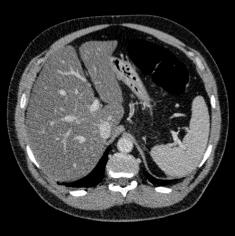

Manually segmenting the hepatic vessels from Computer Tomography (CT) is far more expertise-demanding and laborious than other structures due to the low-contrast and complex morphology of vessels, resulting in the extreme lack of high-quality labeled data. Without sufficient high-quality annotations, the usual data-driven learning-based approaches struggle with deficient training. On the other hand, directly introducing additional data with low-quality annotations may confuse the network, leading to undesirable performance degradation. To address this issue, we propose a novel mean-teacher-assisted confident learning framework to robustly exploit the noisy labeled data for the challenging hepatic vessel segmentation task. Specifically, with the adapted confident learning assisted by a third party, i.e., the weight-averaged teacher model, the noisy labels in the additional low-quality dataset can be transformed from "encumbrance" to "treasure" via progressive pixel-wise soft-correction, thus providing productive guidance. Extensive experiments using two public datasets demonstrate the superiority of the proposed framework as well as the effectiveness of each component.

翻译:将来自计算机地形学(CT)的肝脏船只人工分割,由于船只的低调和复杂形态,由于低调和复杂的形态,造成极端缺乏高质量的标签数据,因此比其他结构更需要专门知识和难度大得多。如果没有足够的高质量的说明,通常的数据驱动的基于学习的方法就会与不足的培训斗争。另一方面,直接引进低质量说明的额外数据可能会混淆网络,导致不良的性能退化。为了解决这一问题,我们提议建立一个新的、由教师协助的、有说服力的、有说服力的学习框架,为具有挑战性的肝脏船只分解任务强有力地利用响亮的标签数据。具体地说,在第三方(即加权平均教师模式)的协助下,经过变通的自信学习后,额外低质量数据集中的噪音标签可以从“阻力”转变为“压力”,通过渐进式的像素方法的软校正,从而提供富有成效的指导。使用两个公共数据集进行的广泛实验,显示了拟议框架的优越性以及每个组成部分的效能。